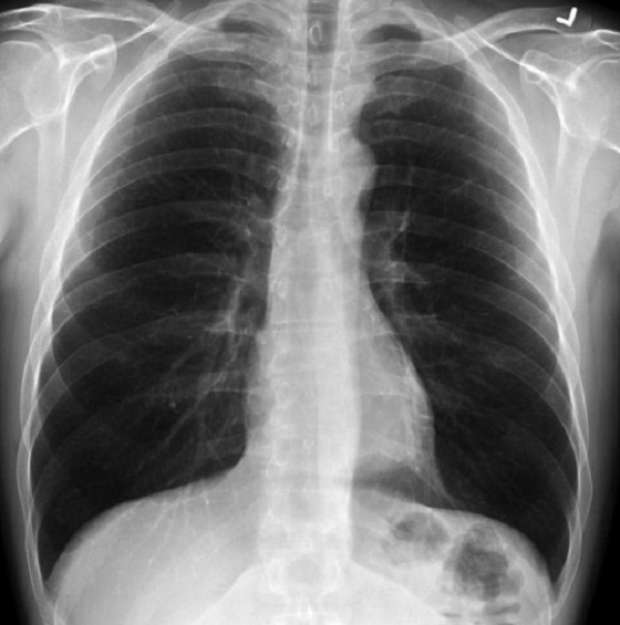

أصيبت امرأة يابانية بأضرار كبيرة في رئتيها بعد أن تسلل فيرس كورونا إلى جسدها، ولإصلاح الوضع، قام الأطباء بما قالوا إنها أول عملية زراعة رئة في العالم لمصاب بفيروس كورونا عن طريق الأنسجة.

وبات معروفا أن مرض “كوفيد-19” يسبب تلفا حادا في الرئة لبعض المصابين به، ولعلاجهم تمت عمليات زراعة رئات لهم لمساعدتهم على التعافي.

وتسببت مرض “كوفيد-19” في أضرار كبيرة لرئتين، وتطلبت عملية زرع رئة حتى تتمكن من العودة إلى الحياة الطبيعية.